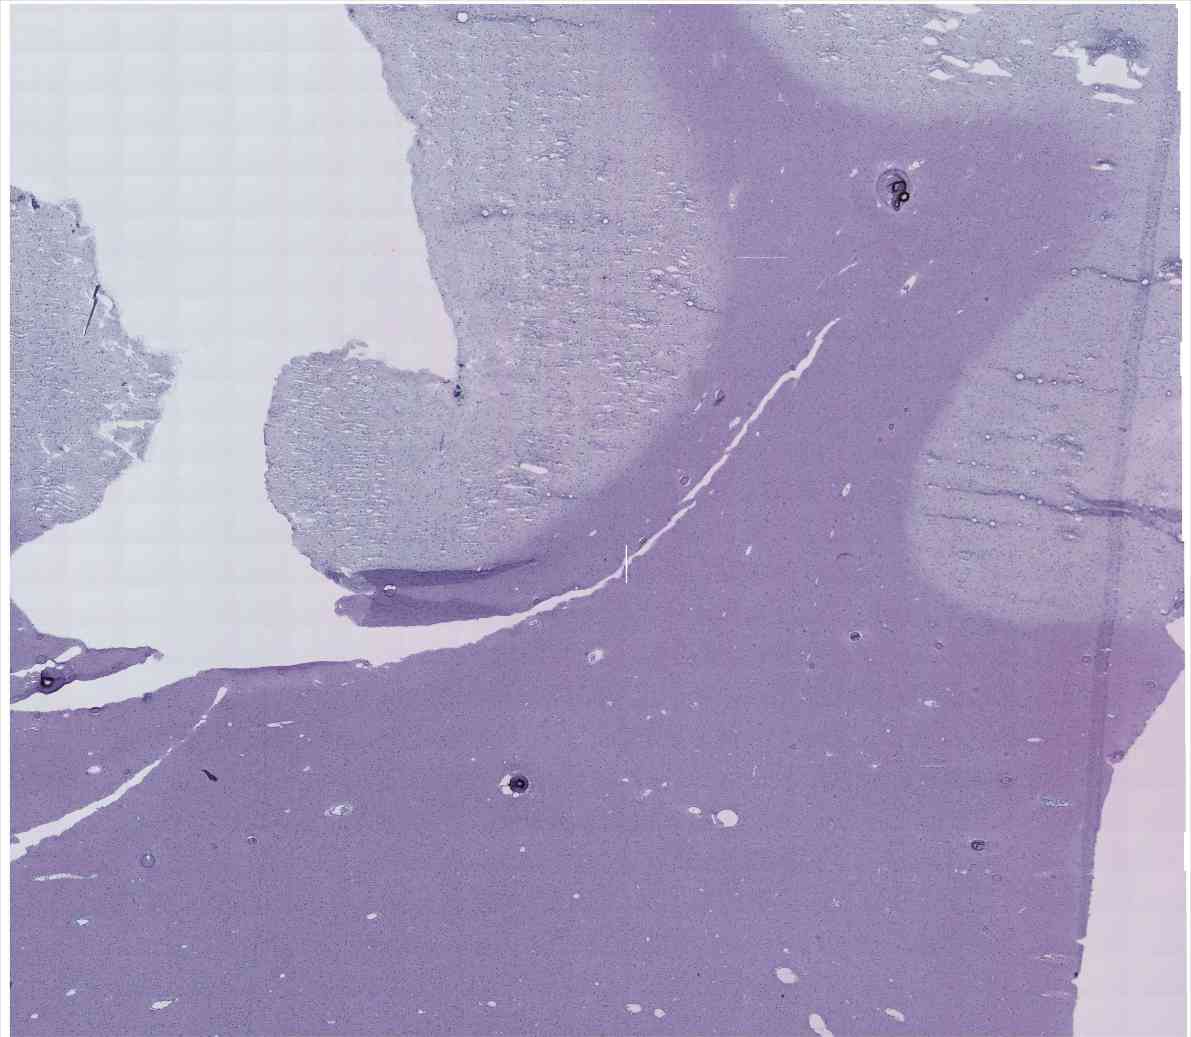

Chip 014 Well D2